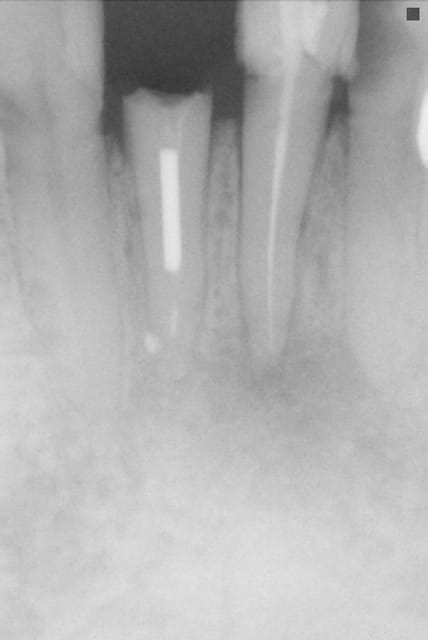

Petite mise a jour, en réalité c'est l'inlay core qui s'est fracturé à 2/3 mm sous l’entrée radiculaire...

(il a croqué dans du pain grillé assez dur a priori c'est déjà comme ça qu'il avait fracturé la dent avant que je la couronne.)

A votre avis c'est récupérable ?

Sinon un bridge a ailette avec un très court ancrage radiculaire dans la racine résiduelle c'est envisageable ???

Honnêtement la je suis un peu démuni...

On n'a qu'une radio du cas mais on peut en tirer pas mal d'enseignement :

la 42 a un gros compo mésial

la 41 est foutue avec réaction apicale

la 31 idem

la 32 présente une carie énorme, qui une fois curetée, ne devrait plus laisser grand chose de plus qu'une racine.

Franchement l'endo sur les incisives inférieures c'est souvent source d'échec, les IC ou tenons sur ces mêmes dents n'en parlons même pas.

Vu la tête de l'endo et la patate au bout de la racine, c'est peut être pas plus mal que l'IC ai cassé...